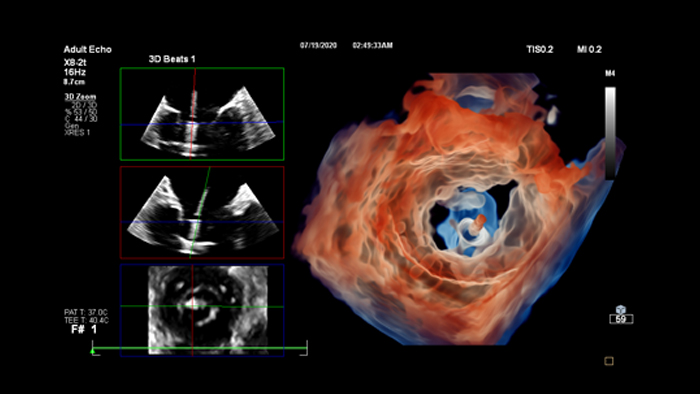

Enhance diagnosis confidence and clinical efficiency through superior image quality, advanced quantification tool and automation technology.